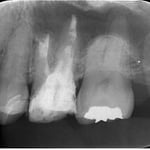

患者さんは何度説明しても虫歯の治療,虫歯の治療と思っていますが,これは根管治療です。上顎第一大臼歯の3本の主たる根管(神経や血管の入っていた管)を神経を取った後に感染を起こし,再治療の際,3本中の2本の管から大量の膿が排出してきた瞬間です。

神経を除去した後でも,その後の処置がしっかりしていないと,管の中に細菌が繁殖し,骨の中に炎症を起こした結果,このように膿が溜り,激痛が生じます。

爪は硬い組織です。ゆえに,詰めの内部で内出血を起こしても,腫れるに腫れられません。ですので,爪に注射針などで穴をあけ,内圧を開放してあげることによって,痛みから解放されます。私自身,体験もしており,痛みが強すぎて,深夜に親指の周囲に麻酔をしたことがあります。歯の根の中の細菌感染によって生じる痛みもまったく同様の理由です。

当然ながら,中古のホースでどこかに劣化があれば,そこから水は漏れます。新品ならば,漏れることろがなくて,ホースは,壊れるまでパンパンに膨らむでしょう。この動画はホースの蛇口を開放してあげた状態です。これで,痛みは徐々におさまります。対処療法としては抗生物質を投与することもありますが,レーザーを当ててもよくはなりません。